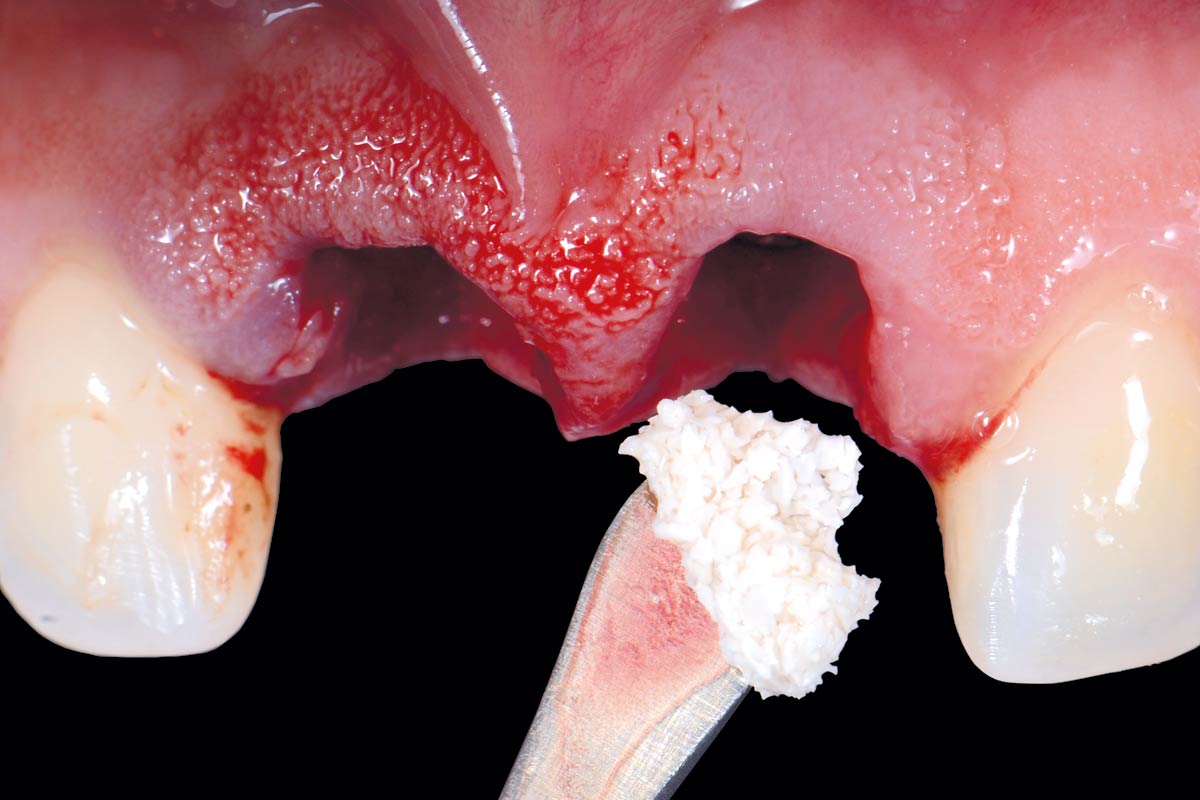

06/12 - cerabone® was used to fill the jumping gap between alveolar wall and implant

Treatment of a double root fracture in the aesthetic zone with cerabone® – Dr. J. M. Abarca